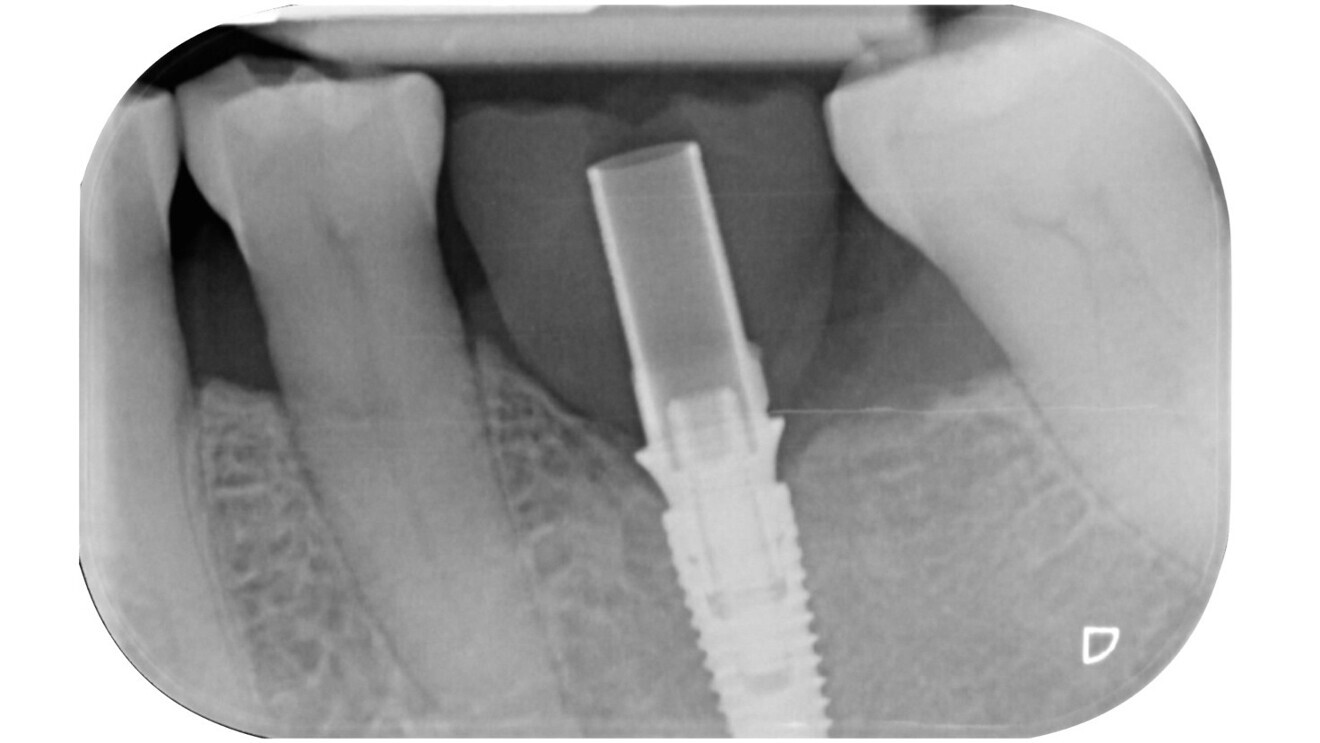

Fig. 1: Radiograph of the single edentulous site in the region of tooth #36 requiring restoration.

Patient assessment and initial situation A 62-year-old female patient presented with a single edentulous site in the mandibular left first molar region (tooth #36; Fig. 1). The missing tooth had been extracted six months previously owing to a vertical root fracture. The patient was in good general health and expressed a desire for rapid and minimally invasive implant-supported rehabilitation. Clinical and radiographic evaluation confirmed sufficient bone volume and soft tissue to allow placement of a standard diameter implant without requiring regenerative procedures.